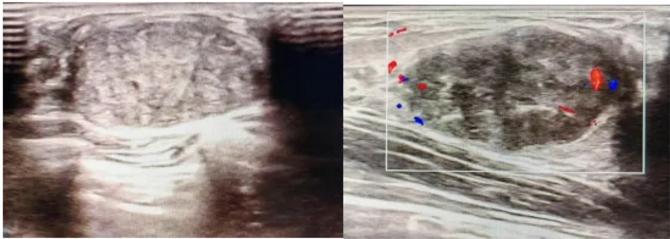

典型表現(xiàn):

橢圓形低回聲團(tuán)塊,包膜完整,內(nèi)部回聲均勻,后方回聲增強(qiáng),周邊無“蟹足樣”浸潤(rùn)。

血流信號(hào):纖維瘤血流較少,惡性常伴豐富雜亂血流。

形態(tài):良性多呈橢圓形或分葉狀,邊界光滑。

縱橫比: 良性通常<1(橫徑>縱徑) 。